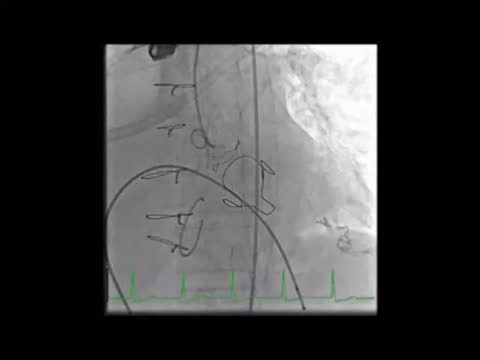

The initial plan was to implant a 23-mm CoreValve Evolut R (Medtronic, Irvine, CA) in aortic position (transfemoral approach) and a 29-mm Edwards SAPIEN 3 in mitral position (transapical approach). The procedure began with a successful left transfemoral approach with a 14-F Fast-Cath sheath, and the left coronary artery was protected with an angioplasty guidewire. Due to extreme difficulty in retrograde crossing of the aorta, a transapical-transfemoral loop approach was considered. The loop was created after gaining transapical access (Figure 2A), through which an INFINITI MPA 2 catheter (5.0 Fr×125 cm, Cordis) was used to advance an Emerald J wire (0.035″×260 cm) anterogradely until it reached the left common iliac artery, where it was captured with a 25-mm Amplatz Goose Neck snare (Figure 2B). After wire externalization at the left groin, the MPA 2 catheter was removed from the apical access and inserted via the groin, enabling the Emerald J wire to be exchanged for an Amplatz Extra Stiff guidewire (0.035″×260 cm) via a left transfemoral route (Video 2). The CoreValve was then successfully advanced into the aortic root and implanted in a suprannular aortic position under rapid pacing (Figure 2C and Video 3), 7 mm below the radiopaque Mitroflow ring. The left coronary ostium was unobstructed. Subsequently, the mitral valve-in-valve Edwards was successfully implanted transapically, without complications (Figure 2D and Video 4). Intraprocedural transesophageal echocardiography showed normal gradients (mean aortic gradient 11 mmHg, mean mitral gradient 3 mmHg) (Figure 2E and F) and a mild aortic perivalvular leak (Video 5). There were no immediate procedural complications. Due to contrast nephropathy and development of anuria (serum creatinine increased to 5.1 g/dl), the patient needed temporary renal replacement therapy, which was discontinued after two and a half weeks due to resumed diuresis. Before discharge, TTE revealed a small paravalvular aortic leak and normally functioning prosthetic valves. The patient was discharged in New York Heart Association (NYHA) functional class II on the 67th day with mild anemia (hemoglobin 11.5 g/dl), creatinine 1.0 mg/dl and eGFR 30 ml/min/1.73 m2.

(A) A long Emerald J wire passes through the stenotic Mitroflow, in which it is captured with an Amplatz Goose Neck snare (B); valve-in-valve implantation of a 23-mm CoreValve Evolut R in aortic position by the transfemoral route (C); implantation of a 29-mm Edwards SAPIEN 3 in mitral position by the transapical route (D); new aortic (E) and mitral (F) bioprosthetic valves visualized by transesophageal echocardiography during the procedure following implantation.